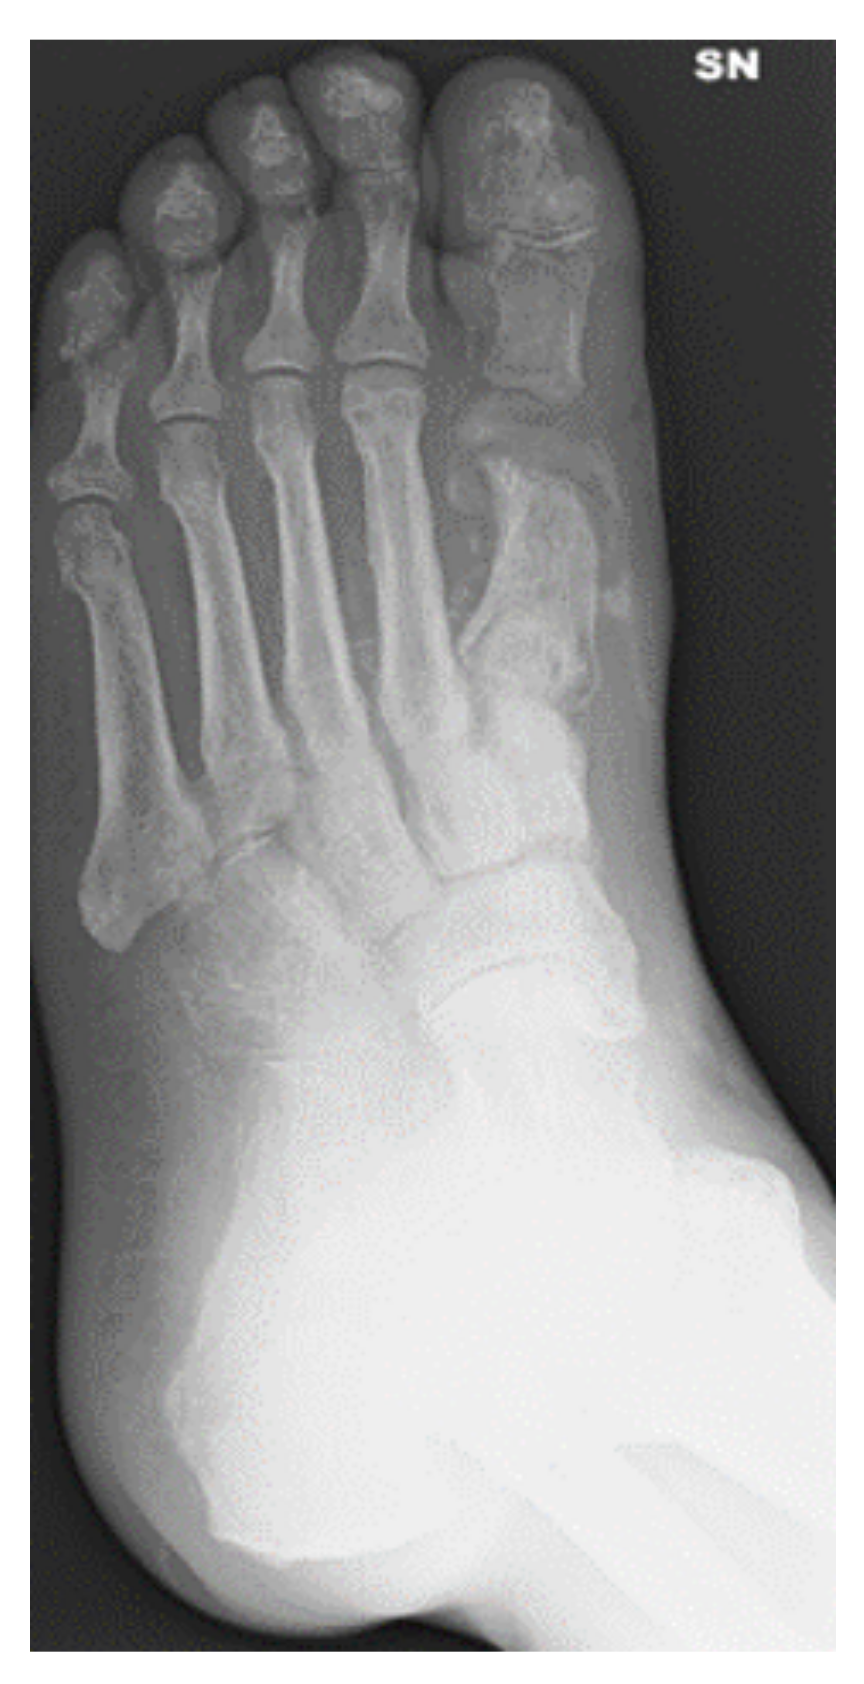

3.3. Lesions Involving Distal Tarsus & Talus